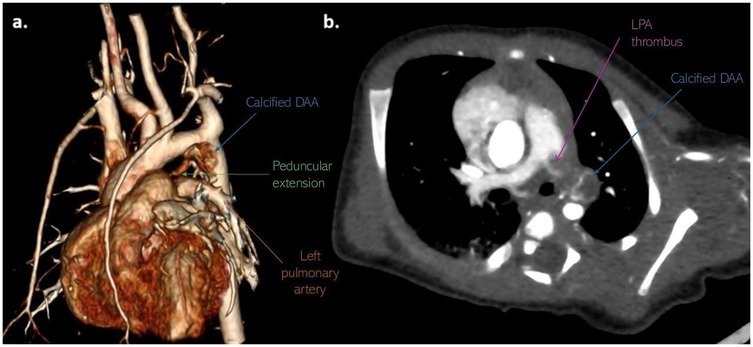

Computed tomography (CT) of the chest with angiography revealed an intraluminal filling defect in the proximal LPA measuring 6 mm × 5 mm, resulting in partial obstruction. A marginally calcified structure was also identified in the middle mediastinum, measuring 13 mm × 6 mm × 8 mm, with a ribbon-like calcified tract extending toward the LPA (Figure 3). No evidence of right heart strain was observed.

Figure 3. Non-gated CT angiography with (a) volume-rendered and (b) axial-oblique reconstructions show marginally calcified DAA (blue arrow) with peduncular extension (green arrow) toward the LPA, as well as thrombotic mass (purple arrow) in LPA. CT, computerized tomography; DAA, ductus arteriosus aneurysm; LPA, left pulmonary artery.